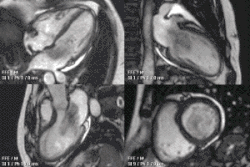

Rather, it is typically used in concert with other diagnostic techniques. In general, the clinical reasons for a CMR examination fall into one or more of the following categories: (1) when echocardiography (cardiac ultrasound) cannot provide sufficient diagnostic information, (2) as an alternative to diagnostic cardiac catheterization which involve risks including x-ray radiation exposure, (3) to obtain diagnostic information for which CMR offers unique advantages such as blood flow measurement or identification of cardiac masses, and (4) when clinical assessment and other diagnostic tests are inconsistent. Examples of conditions in which CMR is often used include tetralogy of Fallot, transposition of the great arteries, coarctation of the aorta, single ventricle heart disease, abnormalities of the pulmonary veins, atrial septal defect, connective tissue diseases such as Marfan syndrome, vascular rings, abnormal origins of the coronary arteries, and cardiac tumors.

Atrial septal defect with dilation of the right ventricle by CMR

Partial Anomalous Pulmonary Venous Drainage by CMR

Enlarged right ventricle with poor function in a patient with repaired tetralogy of Fallot by CMR